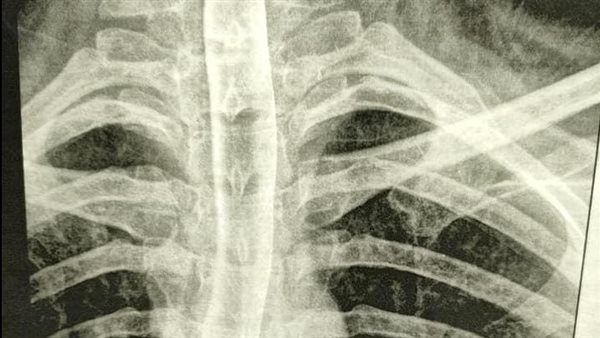

وأكدت مستشفى العبور للتأمين الصحي بكفر الشيخ، أن المريضة بعد تعرضها لحالة الإعياء، أنها توجهت الي استشاري جراحه الصدر الذي تتابع مع فطلب لها اشعه بالصبغة علي المرئ أظهرت وجود التسريب في المرئ فقام بتحويلها الي وحده جراحه الجهاز الهضمي والكبد بالمستشفى منذ شهور.

وأشار بيان مستشفي العبور للتأمين الصحي، أنه تم التعامل مع المريضه وإصلاح الحالة العامه وبدء التغذية الورديه وبروتوكول تسريب المرئ ثم في مرحلة ثانيه تم عمل انبوبه تغذيه معويه بالمنظار الجراحي وتم متابعة المريضه بفريق الوحده والذي يشمل اخصائي تغذية الي تم التئام موضع التسريب والسماح بعودة التغذيه الفمية للمريضة وازاله الانبوبه المعويه ومتابعه حدوث ضيق بالمرئ من عدمه.